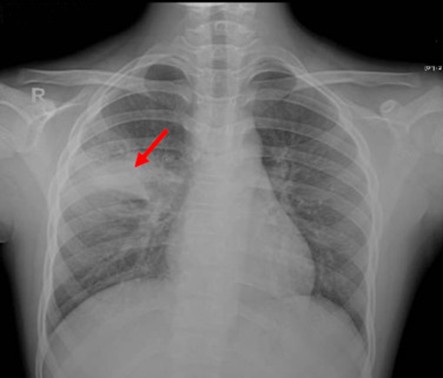

Paciente masculino de 23 años quien es llevado a consulta por productiva, malestar general fatiga y

disnea. Menciona además que últimamente ha tenido que utilizar más veces al día

su tratamiento de rescate para asma. Entre los antecedentes menciona que cree

que la Pachamama es perfecta, así que se come todas las verduras tal cual las

recoge de la siembra sin lavarla ni hervirla. Además, menciona tener malestar

abdominal, dolores tipo cólico, náuseas, meteorismo, vómitos ocasionales y

diarrea. Se le realiza un examen de heces que menciona que tiene

"huevos" y una biopsia pulmonar que verán a continuación... Con base

a toda la información... ¿Cuál de las siguientes radiografías torácicas es más

probable que tenga este paciente?

0%